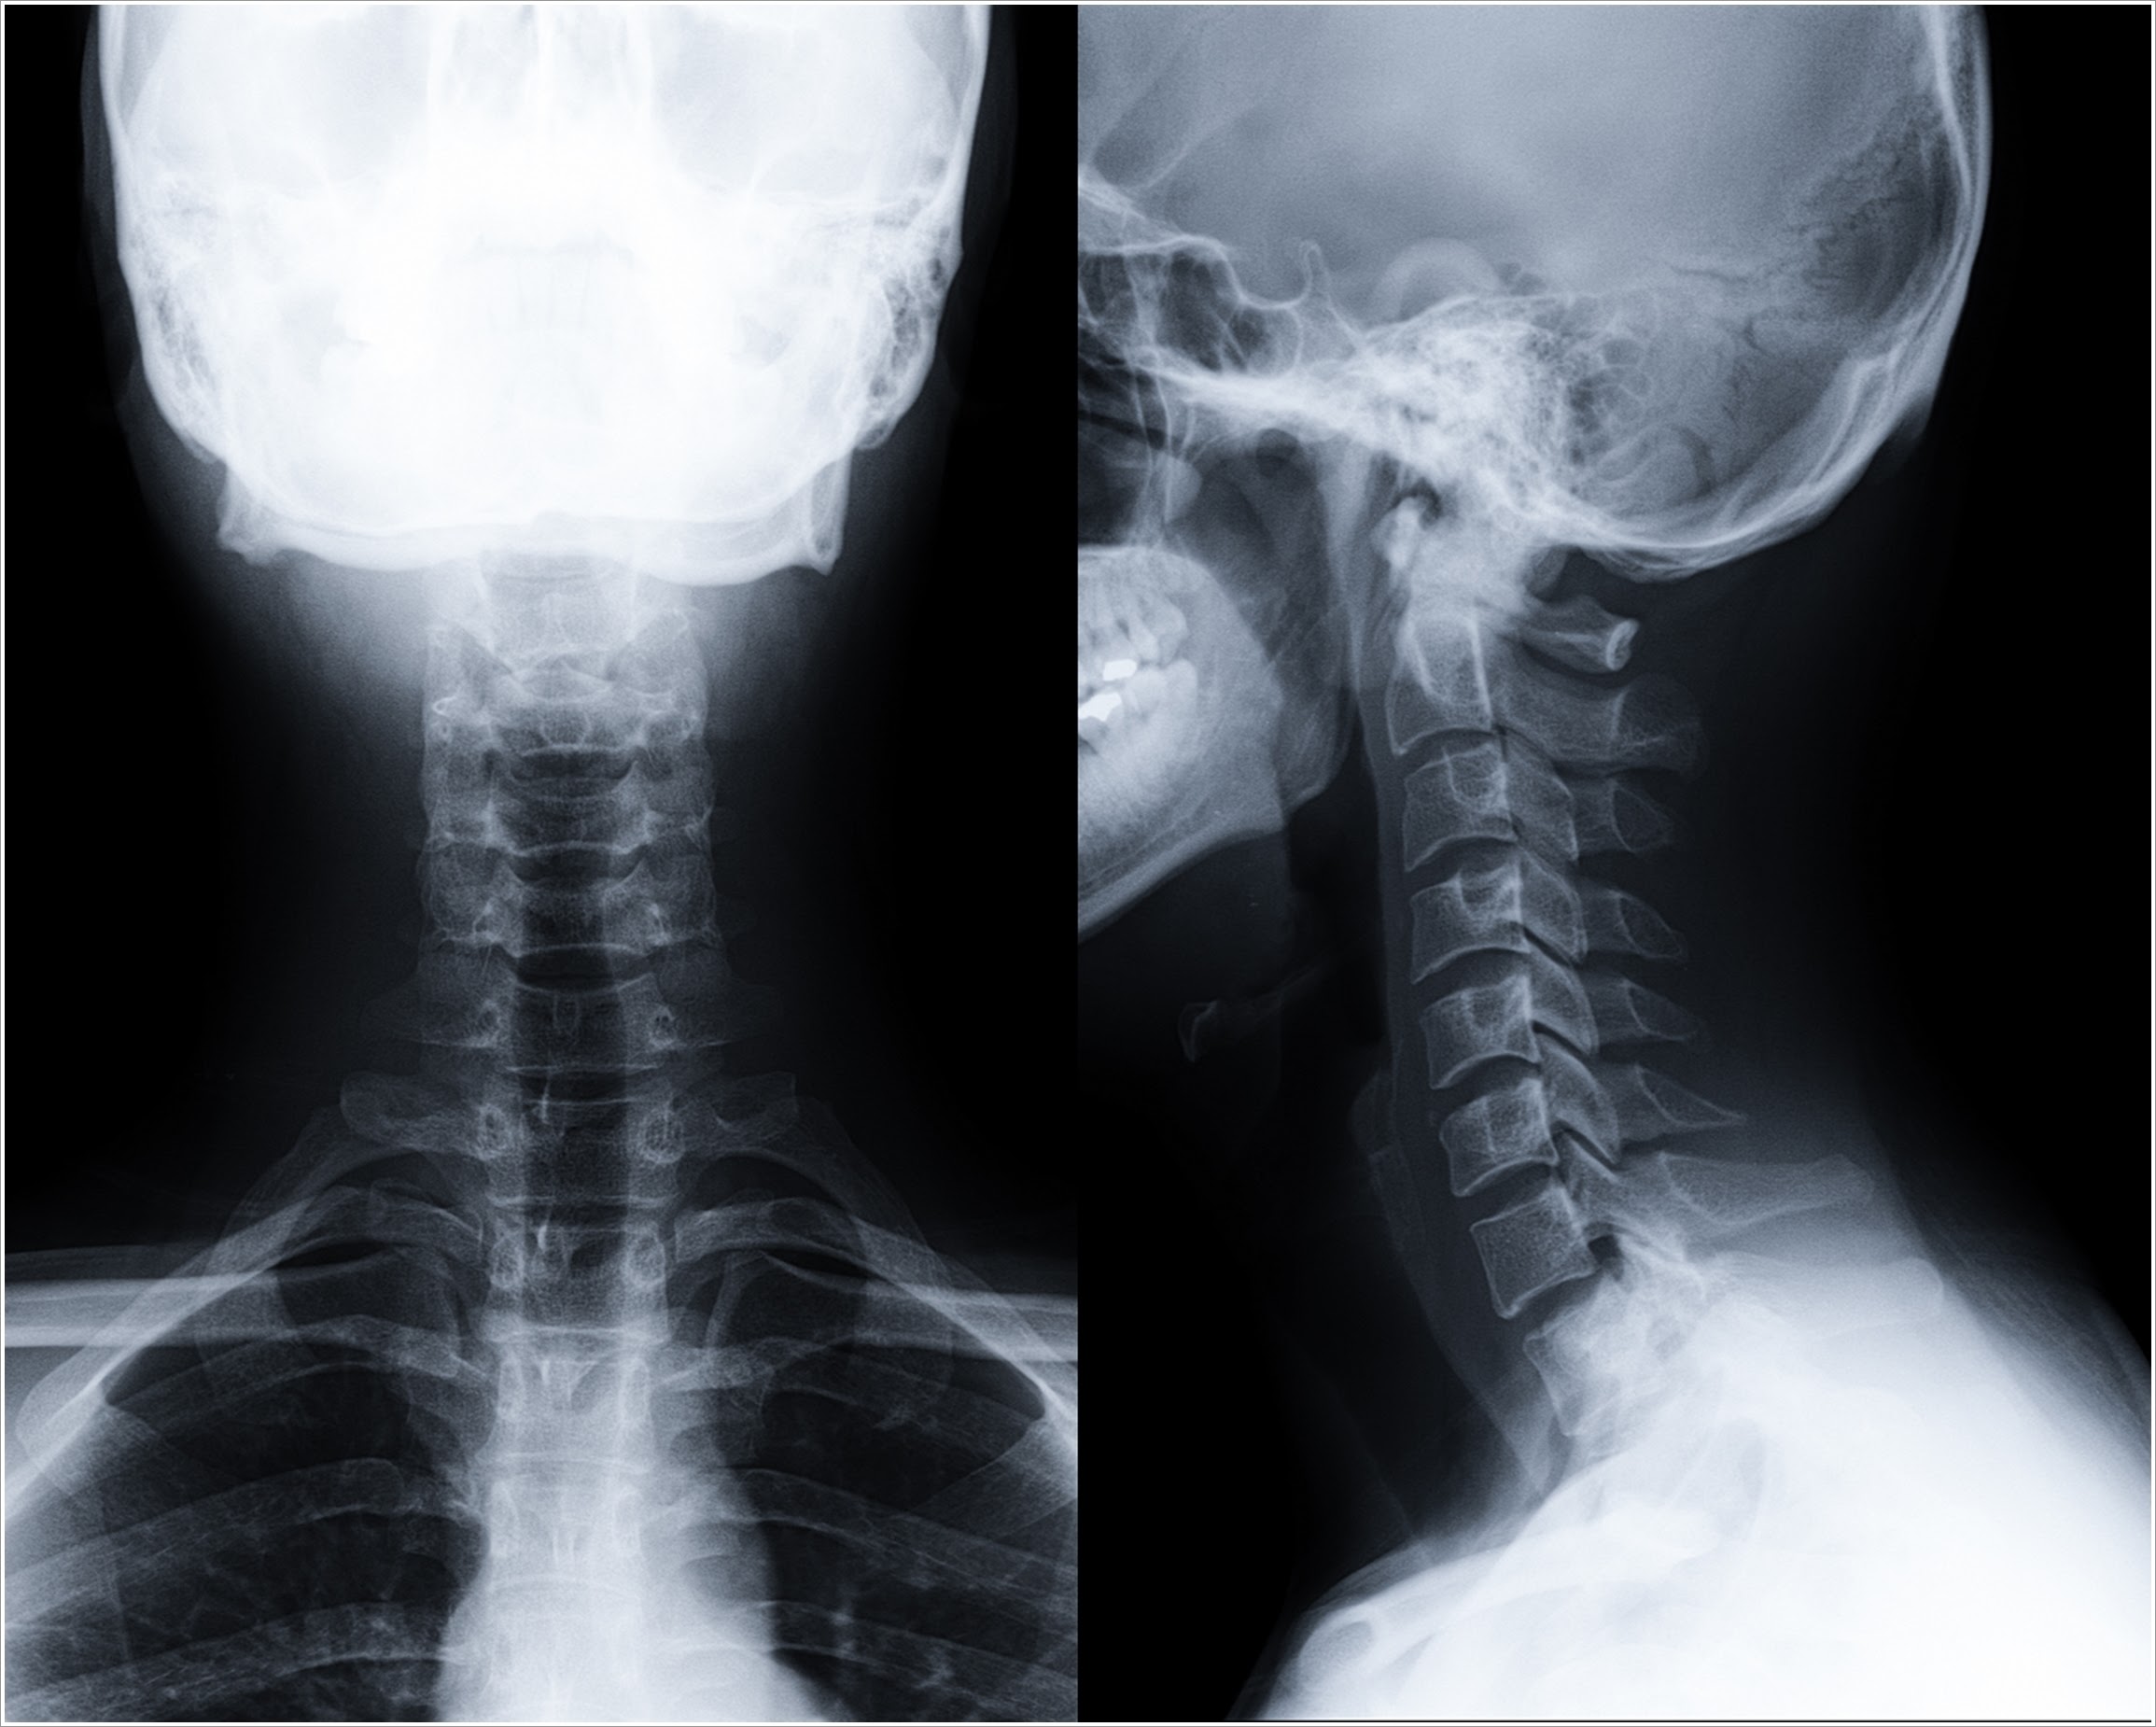

The Cervical Spine AP (Anteroposterior) and Lateral (LAT) Views are standard X-ray projections used to evaluate the vertebrae of the neck. In the AP view, the X-ray beam passes from front to back with the patient facing the X-ray machine. This view shows the alignment of the cervical vertebrae, intervertebral spaces, and spinous processes. In the Lateral view, the beam passes from one side of the neck to the other, providing a side profile of the cervical spine. It clearly displays the vertebral bodies, disc spaces, and alignment, as well as the soft tissue structures. Together, these views are essential for diagnosing fractures, dislocations, degenerative changes, and trauma-related injuries in the cervical spine.

Cervical spine AP/ LAT